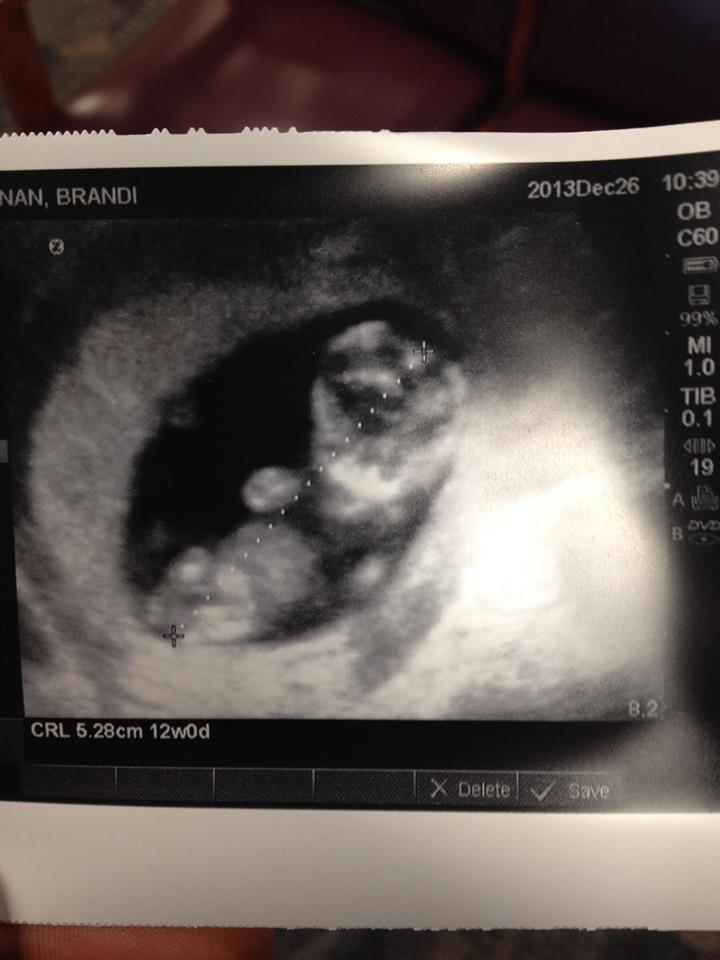

I Have heard of the ramzi theory of the place of the placenta for boy or girl. After two girl on 3 the other 8 months my husband and i decided to try for our boy which will be our last baby...with both my girls we had sex every other day i elevated with my hips under a pillow pointed towards the ceiling did it from behind and i did not orgasm. with this one i only had sex once 12 hours before ovulation stuck baking soda up my you know what orgasmd first did the reverse cowgirl and elevated with my butt in the air since my cervix is towards the front i wanted the semen to fall onto it. the first picture is my first daughter at 12 weeks and the picture is on the abdomen...the second picture is my second daughter at 12 weeks on the abdomen...and the third is the new baby at 8 weeks 4 days through the vagina....any guesses

Attachment 24081Attachment 24082Attachment 24083